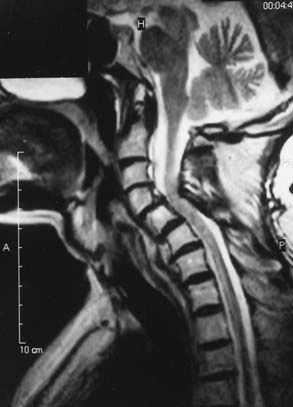

Spinal stenosis is the most common complication of achondroplasia and usually becomes symptomatic in the third decade or later. The anatomy of the achondroplastic spine is distinctive in several respects, all of which contribute to spinal cord compromise and nerve root compression. The superior and inferior articular facets of the vertebral bodies are susceptible to hypertrophy, which results in a “mushroom” shape that is clearly evident on MRI. Abbreviated and thickened pedicles of the vertebral arches result from premature fusion. Intervertebral disks tend to bulge prominently, thus further aggravating neural encroachment by the enlarged vertebral body articular surfaces. The interpediculate distance decreases in the lumbar region of the spine, which results in a canal that tapers caudally, the opposite of normal (the canal normally widens caudally). The overall picture is one of dramatic stenosis in every dimension of the spine (Fig. 219-1).

Although the problems related to hydrocephalus and cervicomedullary compression are frequently identified in infancy and childhood, neurological problems below the foramen magnum are traditionally thought to be manifested in late adolescence and adulthood. However, in our most recent surgical series of 44 pediatric achondroplastic patients who underwent spinal decompressive surgery, over half were younger than 12 years.78 Because the achondroplastic spinal canal tends to have severe congenital constriction, more intensive early screening might reveal substantial numbers of young achondroplastic patients with occult symptoms of spinal stenosis. Estimates of the incidence of symptomatic spinal stenosis range from 37% to 89%, thus suggesting that a significant proportion will eventually have this problem.72 Thorough urologic and neurological testing plays a useful part in the prospective evaluation for occult stenosis. Interestingly, in our pediatric series of achondroplastic spinal stenosis, 27 of 44 (61%) patients who underwent laminectomies for decompression had previously exhibited signs of cervicomedullary compression. In these patients the average age at the time of CMD was 3.5 years, whereas the average age at the time of spinal decompressive surgery was 11.5 years.78